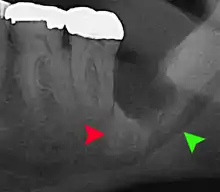

| Diagnostic method | Examination, x-ray |

The diagnosis of impaction can be made clinically if enough of the wisdom tooth is visible to determine its angulation, depth, and if the patient is old enough that further eruption or uprighting is unlikely. Wisdom teeth continue to move to the age of 25 years old due to eruption, and then continue some later movement owing to periodontal disease.[18]

If the tooth cannot be assessed with clinical exam alone, the diagnosis is made using either a panoramic radiograph or cone-beam CT. Where unerupted wisdom teeth still have eruption potential several predictors are used to determine the chance of the teeth becoming impacted. The ratio of space between the tooth crown length and the amount of space available, the angle of the teeth compared to the other teeth are the two most commonly used predictors, with the space ratio being the most accurate. Despite the capacity for movement into early adulthood, the likelihood that the tooth will become impacted can be predicted when the ratio of space available to the length of the crown of the tooth is under 1.[5]: 141